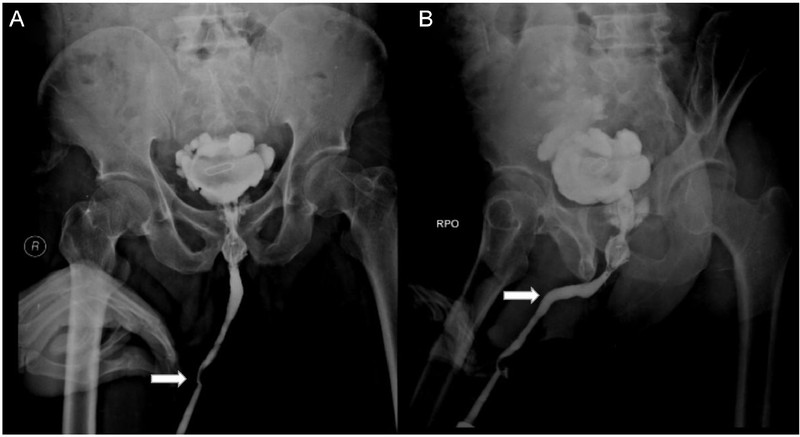

Sebuah hasil rontgen menunjukkan ada sekitar 800 jarum 'susuk' yang bersarang di tubuh seorang wanita. Radiografi perut dari pasien yang sama juga menunjukkan jarum berada paling banyak di area panggul. (Foto: Journal of Radiology Case Reports)

Sebuah hasil rontgen menunjukkan ada sekitar 800 jarum susuk yang bersarang di tubuh seorang wanita. Radiografi perut dari pasien yang sama juga menunjukkan jarum berada paling banyak di area panggul. (Foto: Journal of Radiology Case Reports)